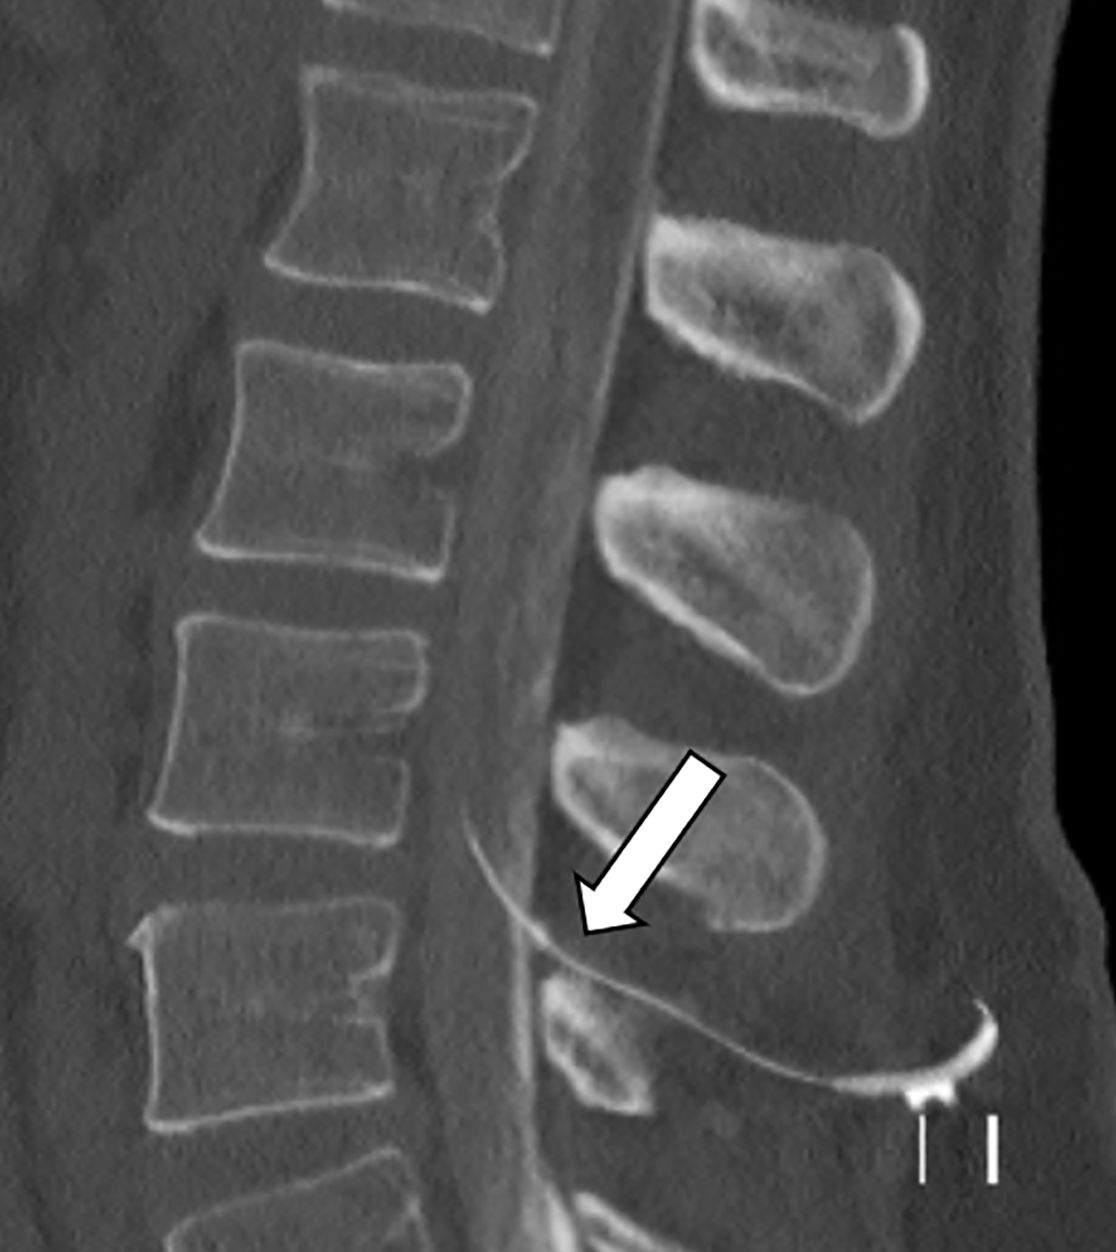

Im Nervenwasserraum (Liquor) einliegender Schlauch zur intrathekalen Therapie (Pfeil)